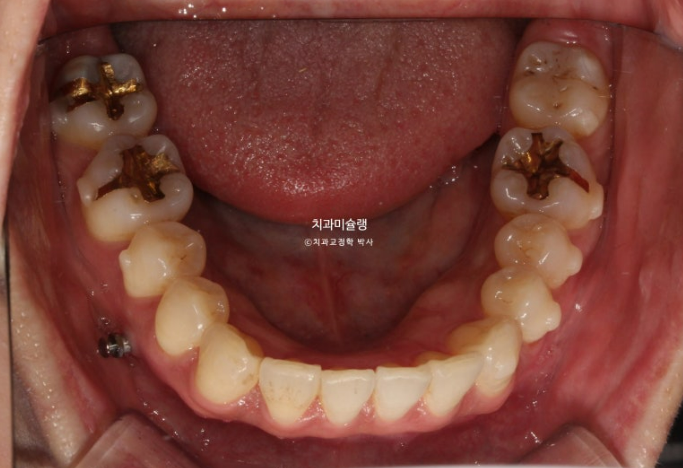

2년 전 교정치료를 위해 온 30대 환자분입니다. 파란 화살표 볼쪽으로 튀어나간 어금니들이 보입니다.

중심선 불일치도 보입니다.

가위교합으로 인한 저작 불편

앞니뻗침으로 인한 돌출이 있고

좌측에는 가위교합이 소구치에 하나 대구치에 하나 총 2군데 있습니다.

교합을 담당하는 어금니 중 절반이 가위교합 상태이니, 좌측으로 씹기가 힘든 상태입니다.

아래 큰어금니는 안으로 쓰러져 있습니다.